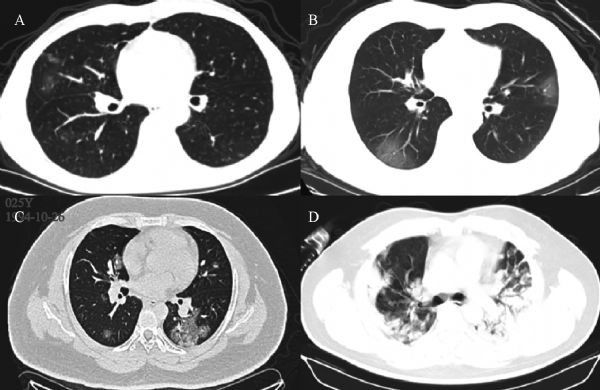

Li Ni, Ling Zhou, Min Zhou, Jianping Zhao, Dao Wen Wang

In December 2019, an outbreak of novel coronavirus (2019-nCoV) occurred in Wuhan, Hubei Province, China. By February 14, 2020, it has led to 66 492 confirmed patients in China and high mortality up to ~2.96% (1123/37 914) in Wuhan. Here we report the first family case of coronavirus disease 2019 (COVID-19) confirmed in Wuhan and treated using the combination of western medicine and Chinese traditional patent medicine Shuanghuanglian oral liquid (SHL). This report describes the identification, diagnosis, clinical course, and management of three cases from a family, suggests the expected therapeutic effects of SHL on COVID-19, and warrants further clinical trials.